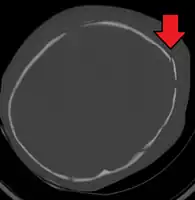

An intraparenchymal bleed with overlying skull fracture from abusive head trauma

Diagnosis can be difficult as symptoms may be nonspecific.[1] A CT scan of the head is typically recommended if a concern is present.[1] While retinal bleeding is common, it can also occur in other conditions.[1] It is unclear how useful subdural haematoma, retinal hemorrhages, and encephalopathy are alone at making the diagnosis.[23]

AHT may be misdiagnosed, underdiagnosed, and overdiagnosed,[26] and caregivers may lie or be unaware of the mechanism of injury.[11] Commonly, there are no externally visible signs of the condition.[11] Examination by an experienced ophthalmologist is often critical in diagnosing shaken baby syndrome, as particular forms of ocular bleeding are quite characteristic.[27] Magnetic resonance imaging may also depict retinal bleeding;[28] this may occasionally be useful if an ophthalmologist examination is delayed or unavailable. Conditions that are often excluded by clinicians include hydrocephalus, sudden infant death syndrome (SIDS), seizure disorders, and infectious or congenital diseases like meningitis and metabolic disorders.[29][30] CT scanning and magnetic resonance imaging are used to diagnose the condition.[11] Conditions that may accompany AHT include bone fractures, injury to the cervical spine (in the neck), retinal bleeding, cerebral bleed or atrophy, hydrocephalus, and papilledema (swelling of the optic disc).[12]